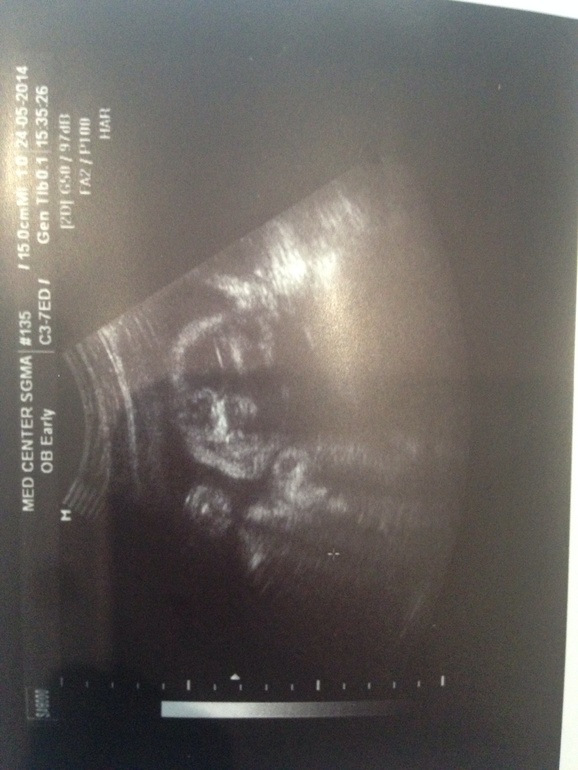

Еще одно событие! Мы вчера прошли удачно УЗИ! наши бедрышки подросли! а то прям генетик запугала нам с малышом, прошлое Узи ей не понравилось и она предположила какие-то отклонения..ттт, все обошлось, у нас здоровый мальчуган полный сил и энергии. Рада я еще , что лежим головкой вниз, хоть он еще будет переворачиваться, но я все равно несказанно счастлива!Зрелость платенты-0, все показатели ттт в норме.

а тут мой сладенький как будто улыбается)) мой маленький улыбаш!